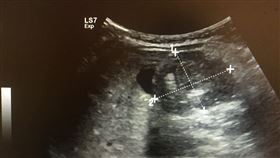

四個月幼兒腸套疊 經搶救後正常解便

四個月大的小BABY,哭鬧斷斷續續,父母親一開始以為...

2021/01/11 13:43